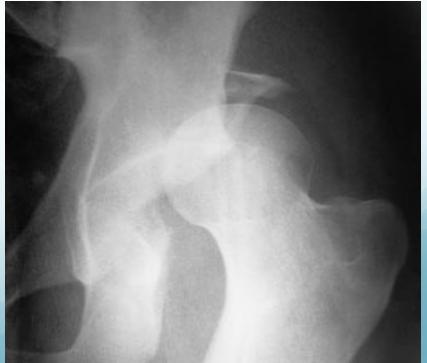

Anterior Hip Dislocation

- Rare

- The leg lies externally rotated, abducted & slightly flexed

- Palpable head in the groin